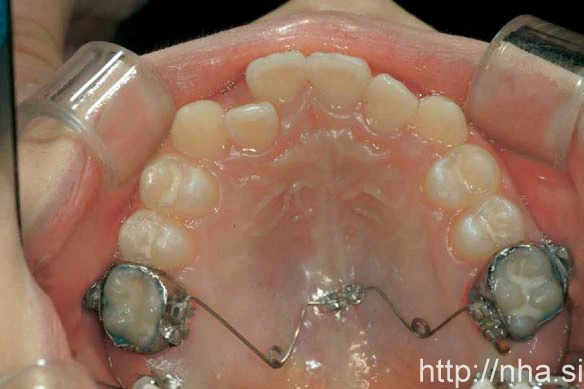

Với điều trị niềng răng mặt trong, minivis có thể được cắm giữa các chân răng ở xương ổ răng phía vòm miệng (Hình 1) hoặc vùng giữa khẩu cái (Hình 2). Ở bệnh nhân là trẻ em, đường khớp giữa khẩu cái vẫn đang mở, trong trường hợp này có thể cắm minivis ở vùng cận giữa khẩu cái (Hình 3). Trong một số trường hợp, có thể cắm minivis ở mặt ngoài ngay cả khi niềng răng mặt trong (Hình 4)

Minivis cắm ở vùng cận giữa khẩu cái

Hình 3 Minivis cắm ở vùng cận giữa khẩu cái.